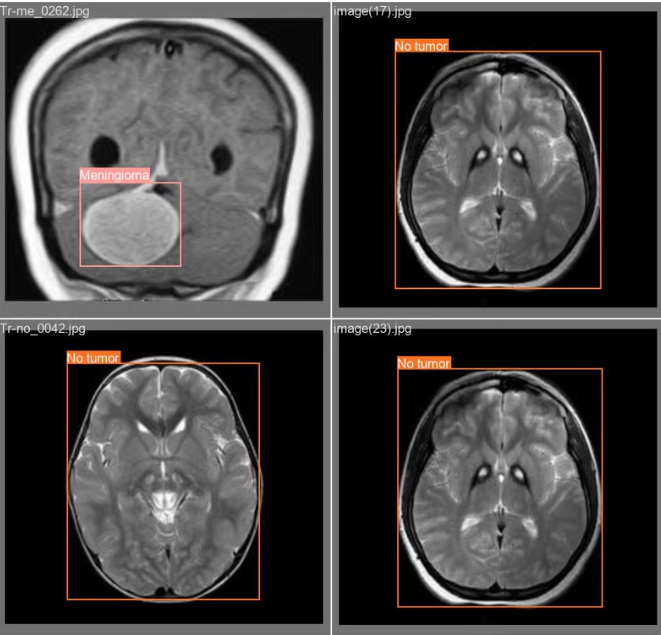

、四种脑肿瘤类别(:胶质瘤、脑膜瘤、垂体瘤和听神经瘤)的检测与分类,我们将从以下几个方面来构建这个

7. 结论

以上代码提供了一个完整的框架,用于构建基于YOLOv8的脑肿瘤检测系统,包括数据处理、模型训练、GUI设计等。根据实际需求,同学;需要调整一些细节,如优化模型参数、增强数据预处理步骤等。